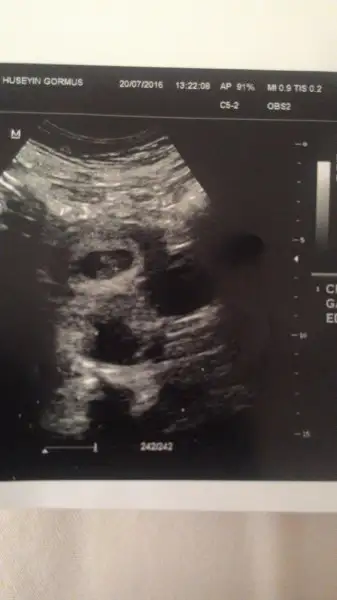

Keseye gore kiz ...Canim buda 9+5 gunluk hali bi bakarmisin karindan bakti dr tekrar bi bakar misjn canjmHavalianne__

Tesekkur ederim canim onceki attigimdad a erkek gibi demisti karidan bakildi ikisi de ay hayirlisi yavv yerim onun totosunuKeseye gore kiz ...

Kiz gibiCanim buda 9+5 gunluk hali bi bakarmisin karindan bakti dr tekrar bi bakar misjn canjmHavalianne__

Aynen sanki sende 3 kese var ucuz gibi :)) bidaki gitmene daha net bisler cikabilir canim benim kuzine ilk gitti hamileyim diye 1 bebeis gibiydi ijinci gittiginde doktor aa bi bebek daha demis sonra ahaa bidaha demis :)) hazirlikli ol 24 haftalik dogdu uvude yasiyo 2 kiz 1 oglan .. senin girunen bebis dedim gibi keseye gore kiz obur arkadasinki farkli onukide erkek keseye gore..Aynen benimde kafama takıldı,sanki başka keselerde varmış gibi,doktor birtane dedi canım,arkadaşlar uğrasa bir yorum yapsalar..